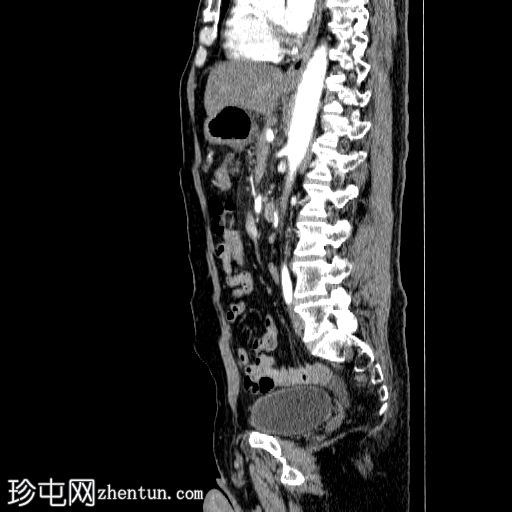

轴向C+动脉期

胰体尾弥漫性增大,特征为胰腺实质低强化,无明显坏死区域。

胰周筋膜平面边界不清的污迹,无明显壁形成、气室、固体碎片或血液产物。

病变横向延伸至左前肾旁间隙,伴有Gerota筋膜增厚。

病变向下延伸至盆腔。

无肠系膜或脾脏血管阻塞的证据。

未见导管扩张或钙化。